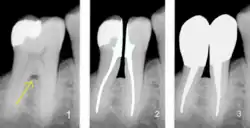

Furkationsgrad

Als Bifurkation (bei zweiwurzligen Zähnen) oder Trifurkation (bei dreiwurzligen Zähnen) wird die Aufteilungsstelle der Zahnwurzeln bei mehrwurzeligen Zähnen bezeichnet. Beim parodontal gesunden Zahn liegen sie innerhalb des Kieferknochens und sind weder sicht- noch sondierbar. Bifurkation und Trifurkation werden in vier Furkationsgrade eingeteilt. Eine freiliegende Furkation, die durch parodontalen Knochenabbau entstanden ist, bildet einen potentiellen Entzündungsbereich, der oftmals schwer zu reinigen ist. Je nach Ausprägung kann eine freiliegende Furkation die Pfeilerwertigkeit reduzieren.[12]

1) Freiliegende Bifurkation (Pfeil);

2) Prämolarisierung und Wurzelkanalbehandlung; 3) Zustand nach Überkronungen mit Stiftaufbauten;

(Darstellung durch Bildbearbeitung);

Hemisezierte oder prämolarisierte Zähne

Unter einer Hemisektion versteht man die Durchtrennung eines unteren Molaren mit einer Teilextraktion einer Zahnwurzel. Bei einer Prämolarisierung erfolgt ebenfalls eine Durchtrennung des Molaren, jedoch bleiben beide Wurzeln erhalten. Aus einem Molar werden dadurch zwei Prämolaren. Die Prämolarisierung ist eine Therapiemaßnahme zur Beseitigung einer freiliegenden Bifurkation. Dabei entsteht aus der Bifurkation ein Interdentalraum (Zahnzwischenraum), der einer Reinigung besser zugänglich ist. Ein hemisezierter oder prämolarisierter Zahn hat nur bei vollständiger Wurzellänge und einem hohen Erhaltungsgrad des verbliebenen Kronenrestes eine Pfeilerwertigkeit 3. Die prämolarisierten Zahnanteile sind in diesem Fall für die Versorgung mittels einer beziehungsweise zweier Kronen geeignet, jedoch nur eingeschränkt als Stützpfeiler für eine Brücke oder herausnehmbaren Zahnersatz.[13]